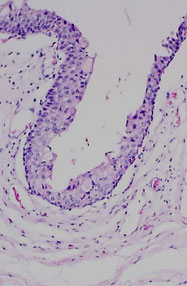

The transitional epithelium of the mucosa appears ragged largely due to post mortem autolytic sloughing of superficial cells.